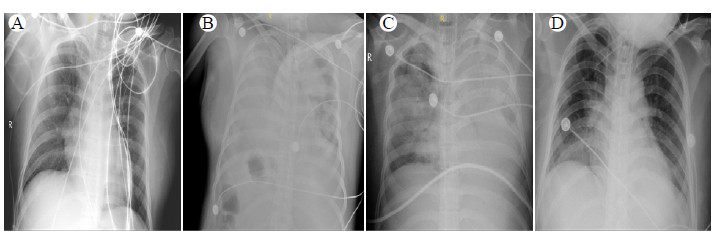

入院第2天,去甲肾上腺素0.6 μg/(kg·min)联合特利加压素160 μg/h下血压93/54 mmHg,心率122次/min,入院9 h液体正平衡2 000 mL。患者渐出现无尿,呼吸窘迫(胸片见图 1A),血气分析示pH 7.169、PO2 125.6 mmHg、PCO2 10.8 mmHg、乳酸7.3 mmol/L、碱剩余-22.4 mmol/L,CVP升至27 mmHg。予气管插管接呼吸机辅助通气,肺保护性通气策略,进行连续性肾脏替代治疗,多巴酚丁胺泵入强心治疗。当天液体正平衡3 091 mL。

| A:入院第2天;B:ECMO上机前(第3天);C:ECMO第2天(第4天);D:ECMO撤机后(第9天) 图 1 患者胸片演变 |

第3天,患者休克加重,去甲肾上腺素上调至1.6 μg/(kg·min),予有创血流动力学提示高排低阻、肺血管通透性增加及肺水肿[心指数4.92 L/(min·m2),全心舒张末期容积指数435 mL/m2,肺水指数14 mL/Kg,肺血管通透性指数4.5,外周血管阻力881 dyn·S·cm-5·m2]。患者渐出现难以纠正的低氧状态,极高呼吸机支持条件(纯氧,呼气末正压15 cmH2O,1 cmH2O=0.098 kPa)联合肌松药以及俯卧位下,血气分析示:pH 7.378、PO2 46.4 mmHg、PCO2 52.2 mmHg、乳酸6.7 mmol/L。胸片提示双肺显著渗出(图 1B)。遂予股动静脉V-A ECMO治疗,初始血流速3.22 L/min,患者血压从100/55 mmHg快速降至69/38 mmHg,右手指脉氧81%。予快速补液,去甲肾上腺素升至2 μg/(kg·min),维持呼吸机纯氧,呼气末正压15 cmH2O,上调ECMO血流量至5 L/min左右后血压渐好转,右手指脉氧渐升至89%左右,足趾脉氧99%。当天液体正平衡2 776 mL。

第4天患者循环好转,特利加压素逐步减停,去甲肾上腺素减量,乳酸降至3.3 mmol/L,右手指脉氧91%,胸片提示肺渗出好转(图 1C)。尿量达1 200 mL/d,实现液体负平衡,并渐降低呼吸机支持条件。第7天,患者右手指脉氧100%,ECMO支持条件下调。第9天,患者停用升压药,CVP 13 mmHg,ECMO及连续性肾脏替代治疗顺利撤机(图 1D),查超声心动图无异常。第13天,患者情况稳定,予脱机拔管,2 h后呼吸窘迫,予再次气管插管机械通气,拔管失败考虑与气道狭窄有关。第17天患者气囊漏气试验仍无法通过,予气管切开,床边活动。第25天床旁电子喉镜发现右侧声门下见新生物,考虑阻塞性纤维蛋白气管伪膜。第31天,患者带气切导管出院,定期随访。一个月后患者活动如常,门诊查超声心动图及胸部影像学无异常,喉镜示声门下新生物消退,予气切封管。一年后随访患者无不适,正常生活。